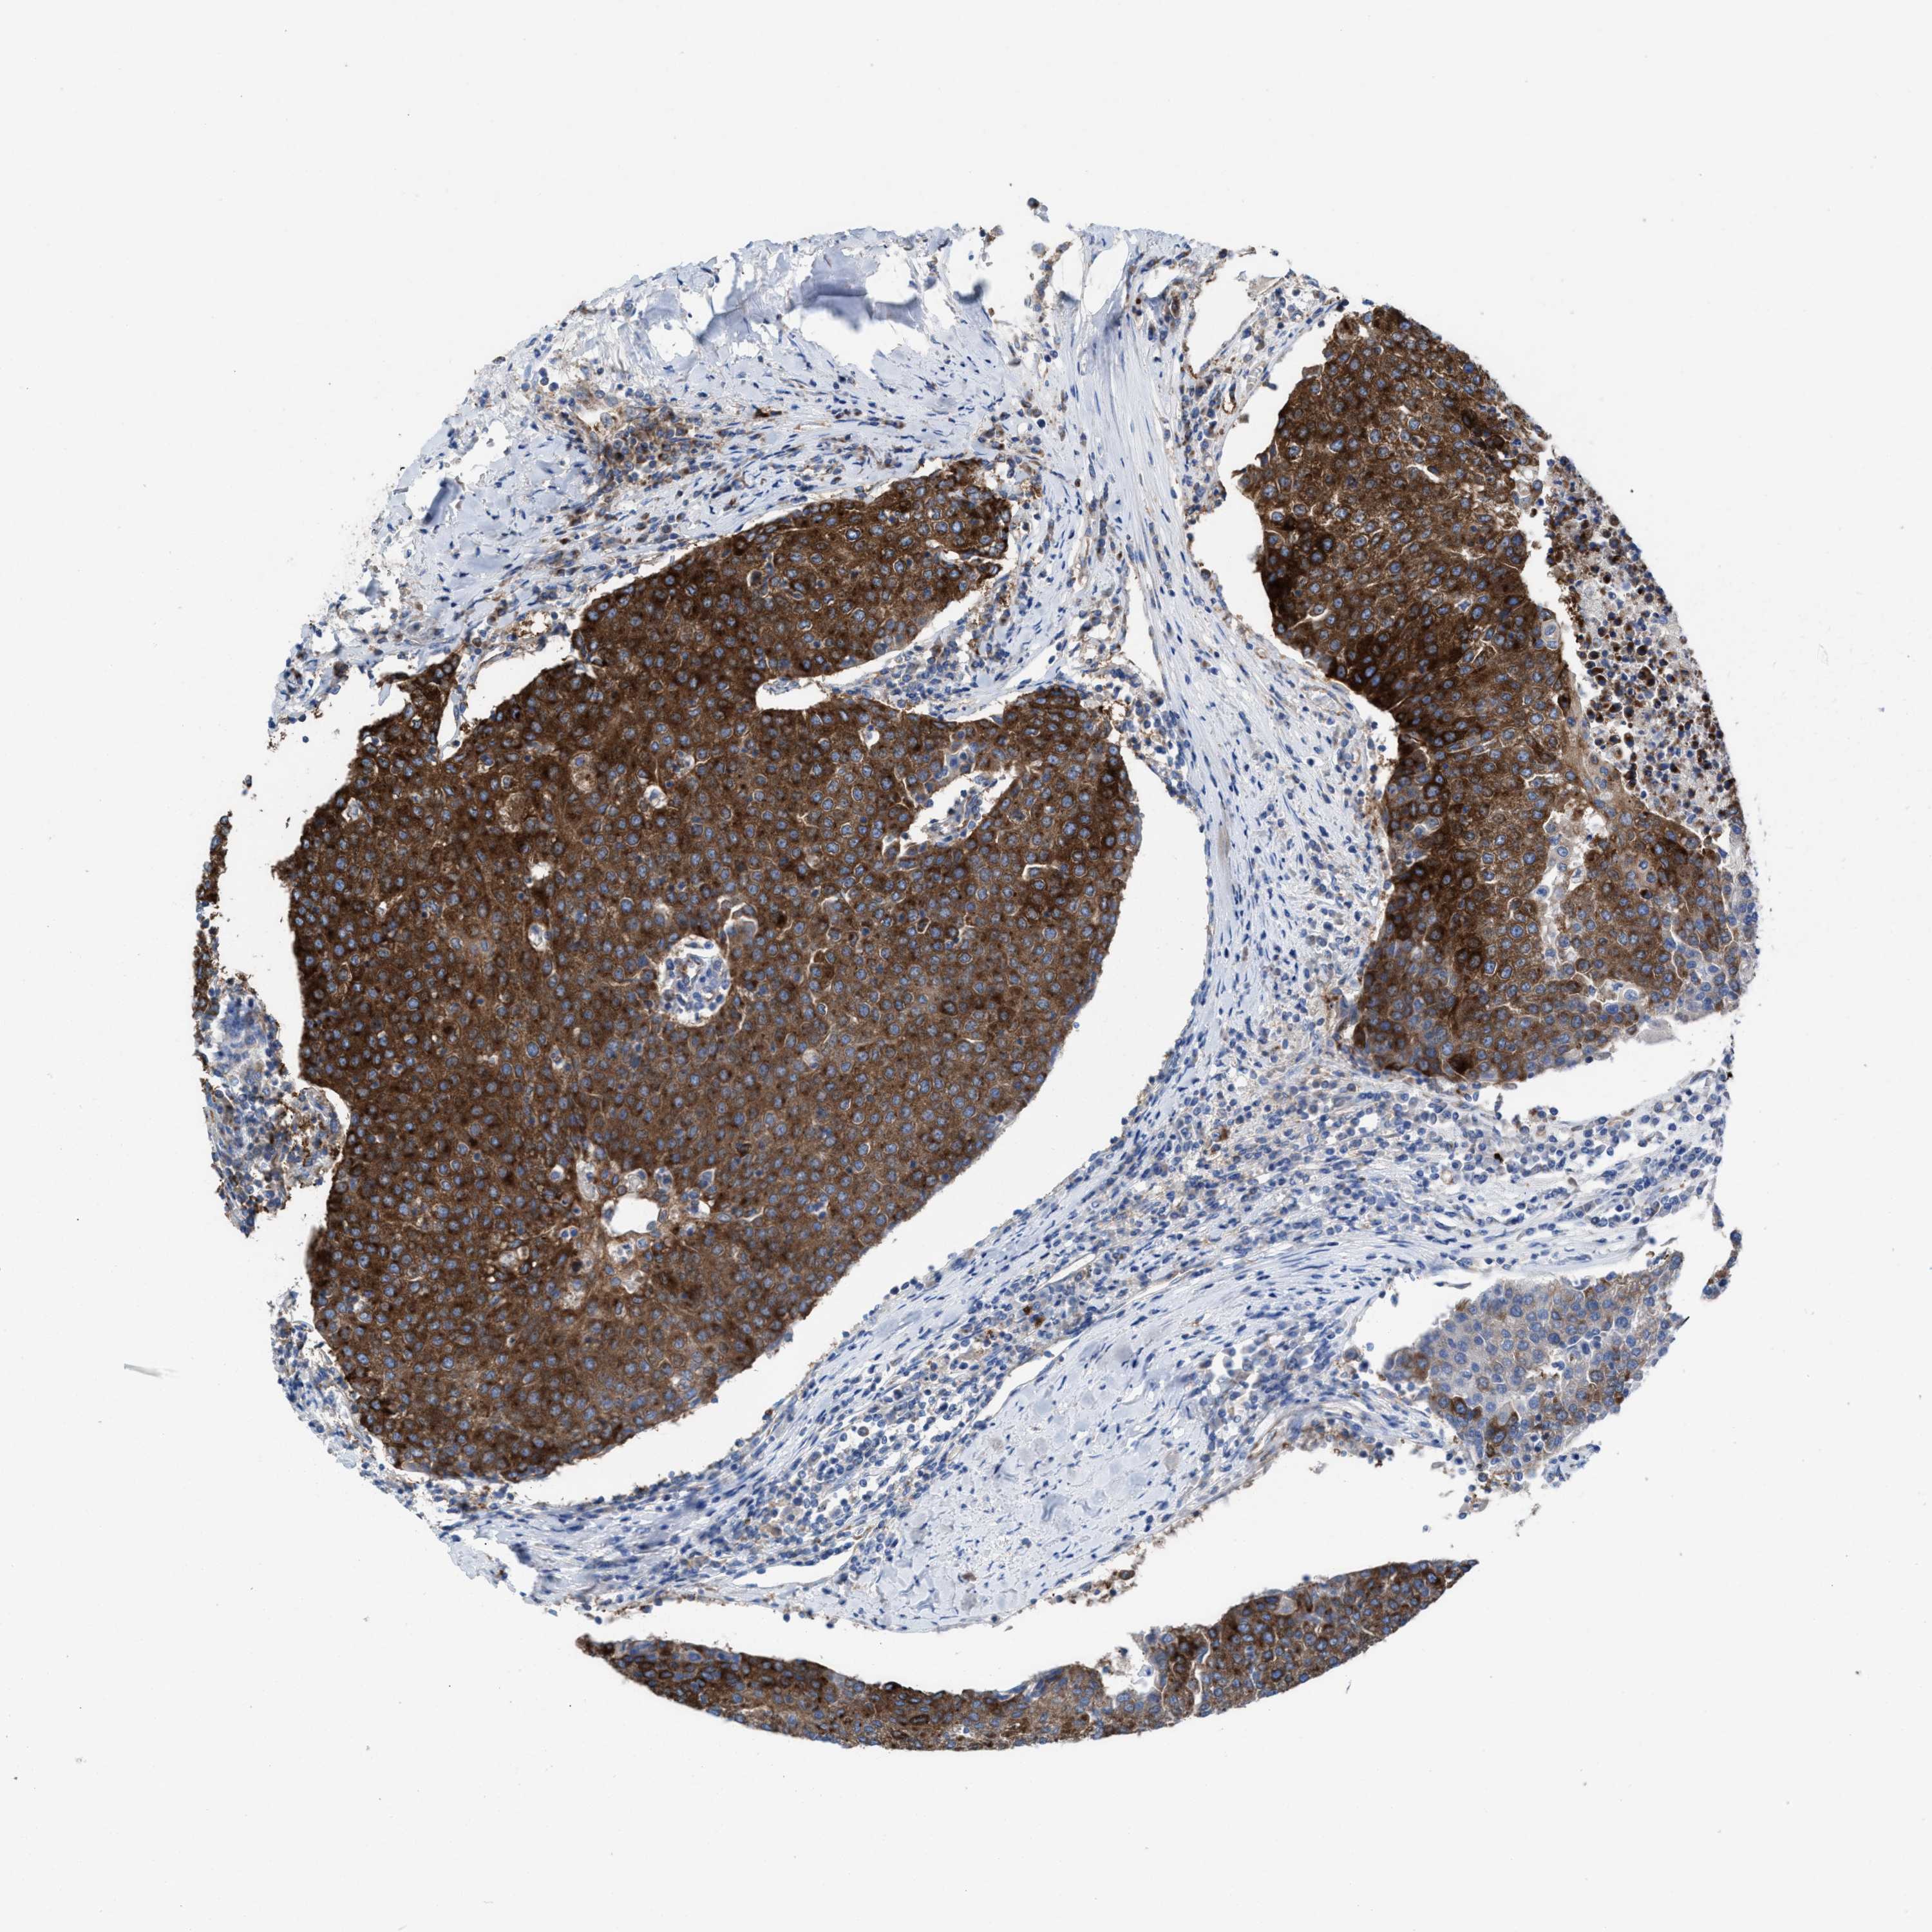

UROTHELIAL CANCER - Protein expressioni

A mouse-over function shows sample information and annotation data. Click on an image to view it in a full screen mode. Samples can be filtered based on level of antibody staining by selecting one or several of the following categories: high, medium, low and not detected. The assay and annotation is described here.

Note that samples used for immunohistochemistry by the Human Protein Atlas do not correspond to samples in the TCGA dataset.

Antibody stainingi

Antibody staining in the annotated cell types in the current human tissue is reported as not detected, low, medium, or high, based on conventional immunohistochemistry profiling in selected tissues. This score is based on the combination of the staining intensity and fraction of stained cells.

Each image is clickable and will lead to virtual microscopy that enables deeper exploration of all samples and also displays staining intensity scores, fraction scores and subcellular localization as well as patient and tissue information for each sample.

Antibody HPA022251

Staining

High

Medium

Low

Not detected

Intensity

Strong

Moderate

Weak

Negative

Quantity

>75%

75%-25%

<25%

None

Location

Nuclear

Cytoplasmic/membranous

Cytoplasmic/membranous,nuclear

Urothelial carcinoma, Low grade

Urothelial carcinoma, High grade